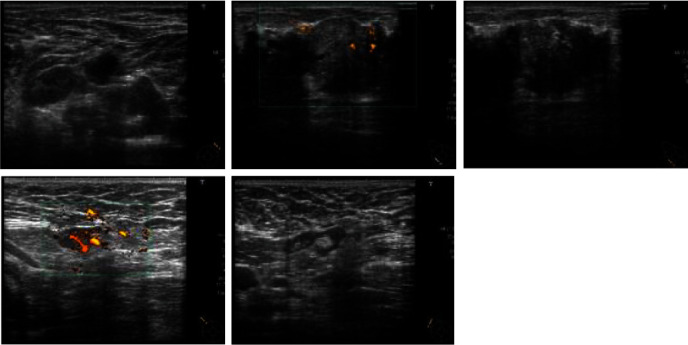

自身免疫性中性粒细胞减少症(AIN)是一种极为罕见的疾病,目前尚无有效的治疗方法。自身免疫性中性粒细胞减少症可导致围手术期感染等重大并发症。在此,我们介绍一位 56 岁的女性患者,她原计划接受乳腺癌手术。然而,她却意外地被诊断出患有 AIN。因此,手术被推迟,并开始接受内分泌治疗。治疗 7 个月后,她接受了手术。手术前注射了粒细胞集落刺激因子,但患者的中性粒细胞计数没有增加。因此,在手术中使用了左氧氟沙星。术后 1 天,患者出现发热(38.6°C)。她的手术伤口没有发红,也没有其他感染迹象。术后第二天烧退了。尽管如此,她仍服用了 5 天抗生素。患者于术后第六天出院。

Autoimmune neutropenia (AIN) is an extremely rare condition, and there is no effective treatment option for this disorder. AIN can cause major complications in patients with perioperative infection. Herein, we present a 56-year-old female patient who was scheduled for breast cancer surgery. However, she was unexpectedly diagnosed with AIN. Thus, the surgery was postponed, and endocrine therapy was started. After 7 months of treatment, the surgery was performed. Granulocyte colony-stimulating factor was administered before the surgery, but the patient's neutrophil count did not increase. Thus, levofloxacin was administered during the surgery. The patient had fever (38.6°C) 1 day after the surgery. Her surgical wound did not present with redness, and there were no other signs of infection. The fever subsided on the second day after the surgery. Nevertheless, antibiotics were administered for 5 days. The patient was discharged on the sixth day after the surgery.